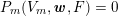

Figure 3.1. Possible choices of the Dirichlet and Neumann boundaries (a) and physical and artificial boundaries (b) for a carotid domain in the fluid stand-alone problem (reconstructed from MRA images).